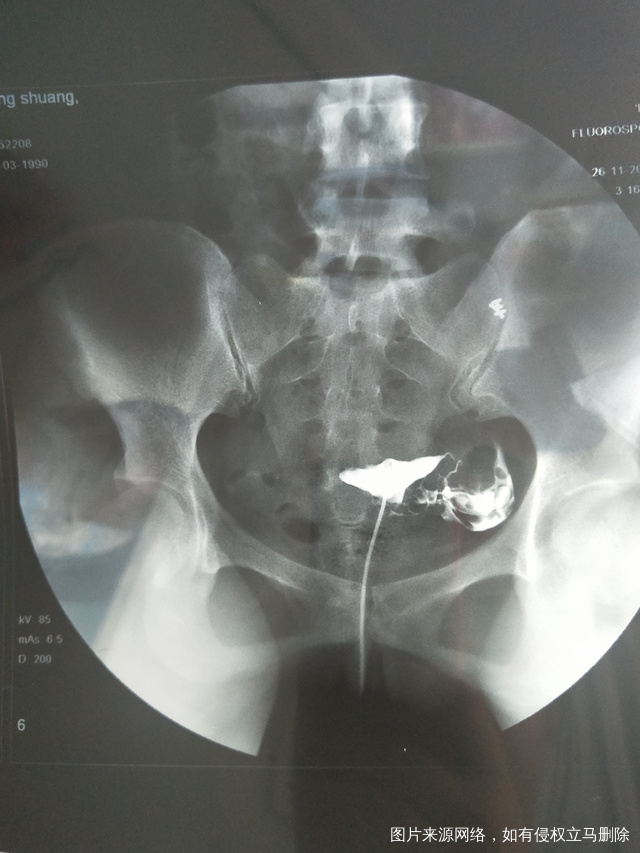

做完输卵管造影第六天了小腹还是感觉沉甸甸的如

可以热敷腹部,如果有发热,腹痛加剧,白带量多,有异味,随时就医